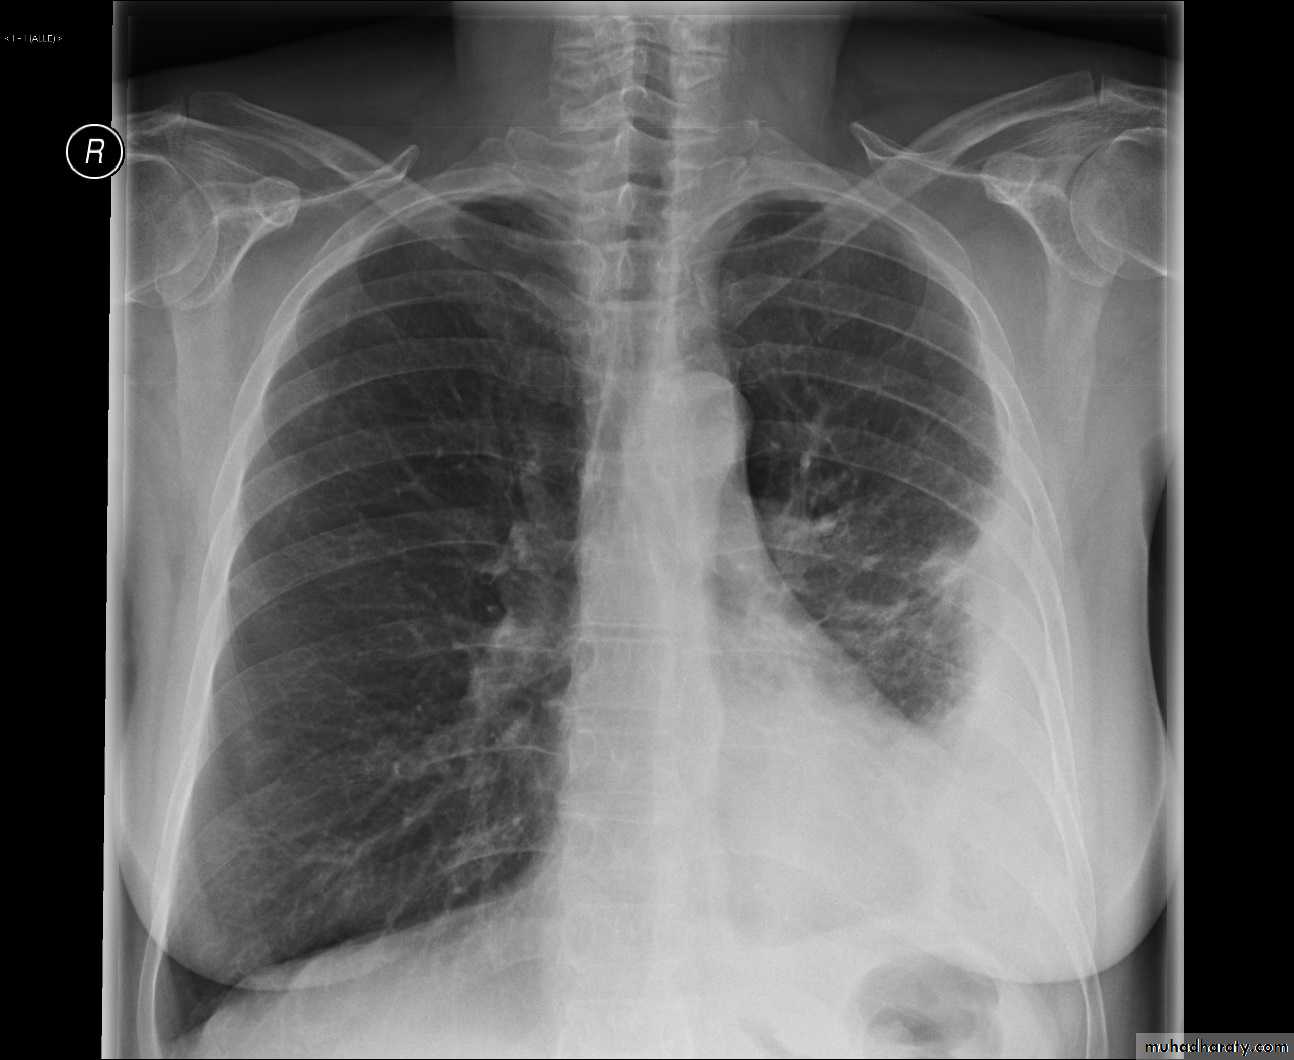

Hemothorax

X-ray hemothorax

X-ray pneumohemothorax